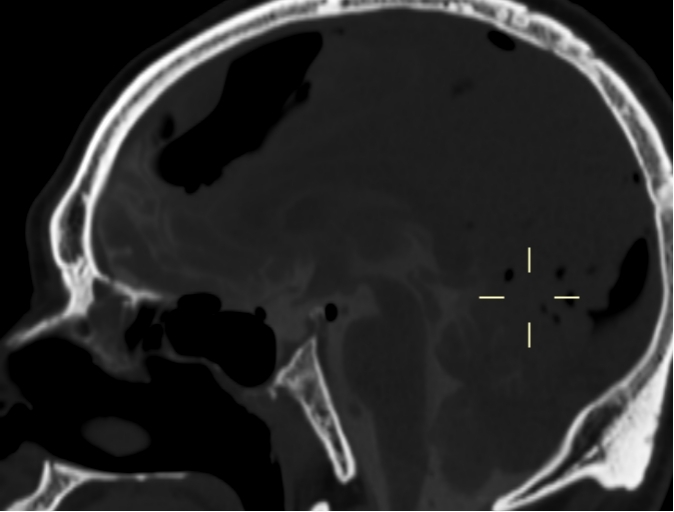

我院PET-CT检查显示鼻咽周围骨质改变,未见异常代谢增高,无肿瘤复发;左侧颞叶、左侧岛叶及左侧鞍旁片状低密度影,伴代谢稀疏,提示放射性坏死。脑室造影检查显示颅内积气,前颅底鞍结节颅骨缺损,脑脊液漏可能(图1-3)。MRI检查显示左侧颞叶内侧面不规则强化病灶,考虑放射性脑坏死改变(图4)。